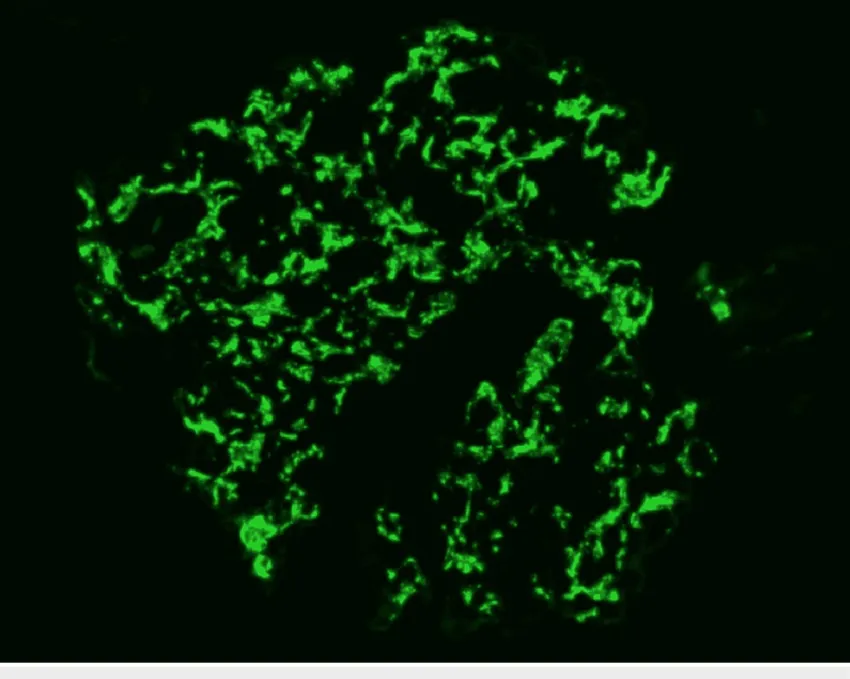

A glomerulonefrite por C3 (GNC3) resulta de ativação descontrolada da via alternativa do complemento e pode simular uma GN pós-infecciosa. O diagnóstico correto depende do reconhecimento do padrão de deposição de C3 e da investigação genética. Com terapias-alvo como o eculizumabe e o iptacopan, identificar precocemente a GNC3 pode mudar o desfecho do paciente.